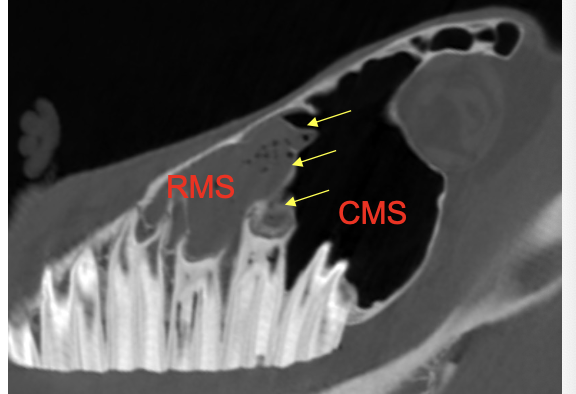

What are the groups and names of the paranasal sinuses?

Rostral group (2 sinuses)

Rostral maxillary (RMS)

Ventral conchal (VCS)

Caudal group (5 sinuses)

Caudal maxillary (CMS)

Frontal (FS)

Dorsal conchal (DCS)

Sphenopalatine (SP)

Ethmoid sinus (ES)

Why does dental disease cause secondary sinusitis?

Close proximity of alveolar bone to maxillary sinuses

Upper 08/09s —> Rostral Maxillary Sinus (RMS)

Upper 10/11s —> Caudal Maxillary Sinus (CMS)